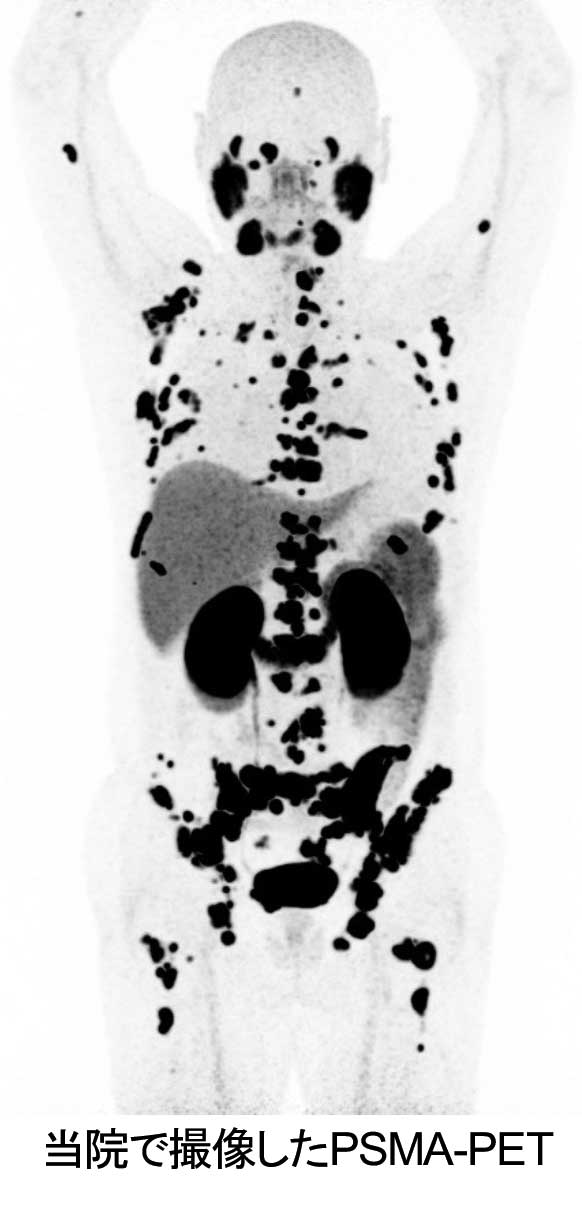

最新の半導体PET/CT装置で撮像いたします。

右図のような非常に鮮明な画像を撮像することが可能です。